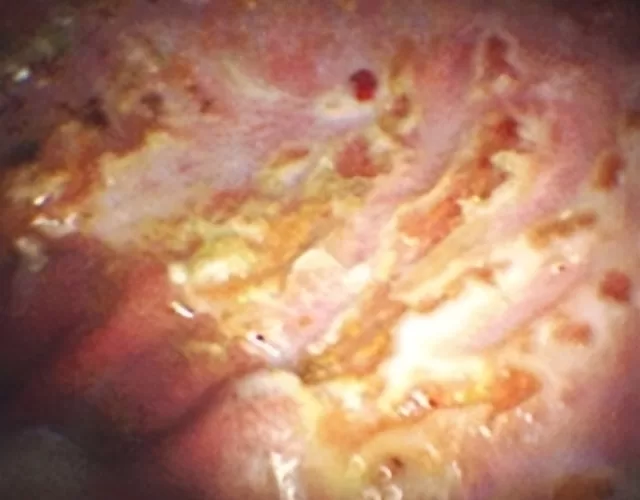

Gastric ulcers can span a wide variety of severity from mild inflammation of the stomach lining through to severe, bleeding ulcers and even perforation of the stomach – which can be fatal. The only way to definitively diagnose and grade ulcers is by gastroscopy to view the lining of the stomach.

The images below show the difference between a normal stomach and a stomach suffering from ulcers.